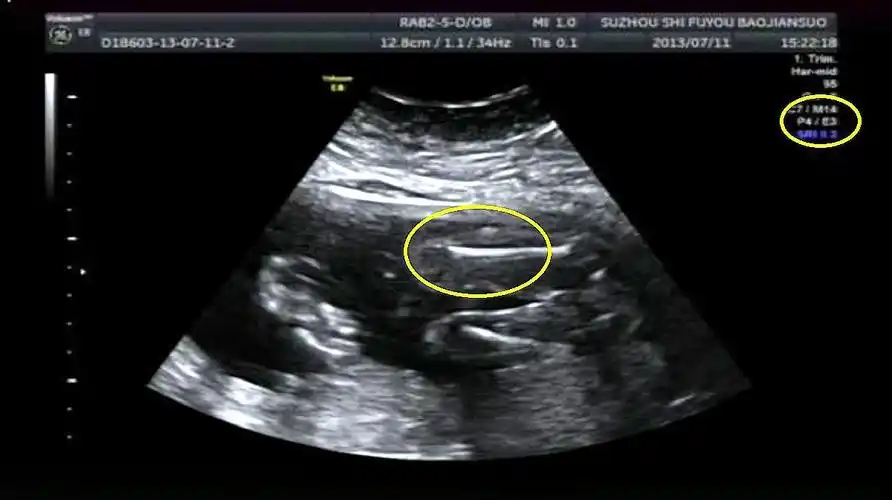

金龟子女儿晒b超照宣怀孕3月疑男孩,与14岁初恋67牵手像带孩子_网友

辨别胎儿性别有方法,b超单上一清二楚,再也不用求医生了!

孕期检查,b超单上出现这3组数据,或许代表怀了位"小男宝"_胎儿_进行